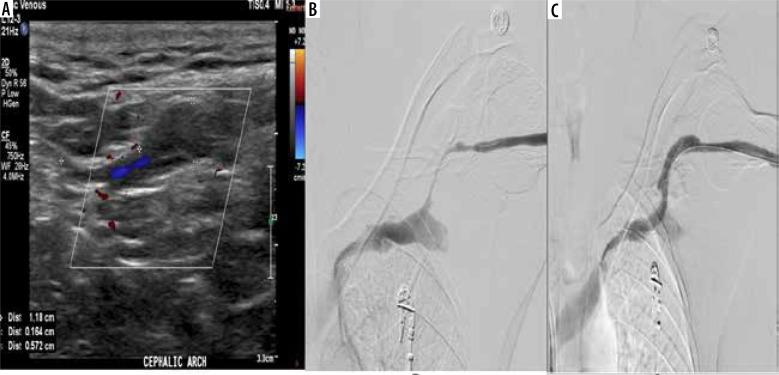

Results: Inter-observer agreement regarding complications of AVF/AVG was very good for the identification of thrombus (κ = 1.0), seroma (κ = 0.953), aneurysm (κ = 0.851), and pseudoaneurysm (κ = 0.851). It was considered good for the detection of juxta-anastomosis stenosis (κ = 0.751) and feeding artery stenosis (κ = 0.638). However, he agreement was fair for identifying draining vein stenosis (κ = 0.380) and distal arterial steal syndrome (κ = 0.210). The overall diagnostic performance of CDUS exhibited 86% sensitivity in identifying stenosis, with a specificity of 99.1%, a positive predictive value (PPV) of 96.5%, a negative predictive value (NPV) of 97%, and an accuracy of 94.3%.

Conclusions: CDUS is a noninvasive diagnostic approach for the prompt picking of AVF complications. It serves as a suitable first-line imaging modality for nonfunctional AVF due to its cost-effectiveness and accessibility. Additionally, we provide evidence of reproducibility, encouraging the diligent use of CDUS in AVF and AVG evaluation for early complication detection and management guidance.